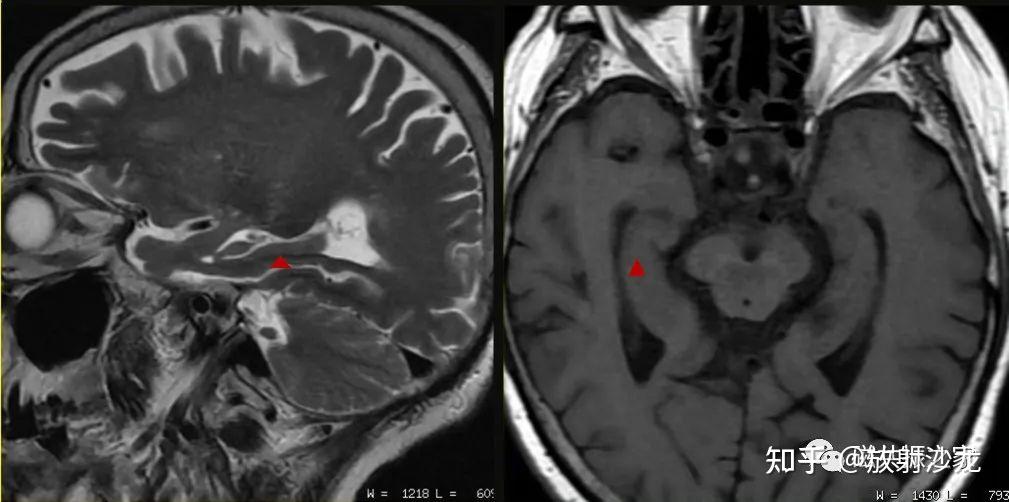

海马硬化的影像诊断

影像复习海马硬化的影像诊断